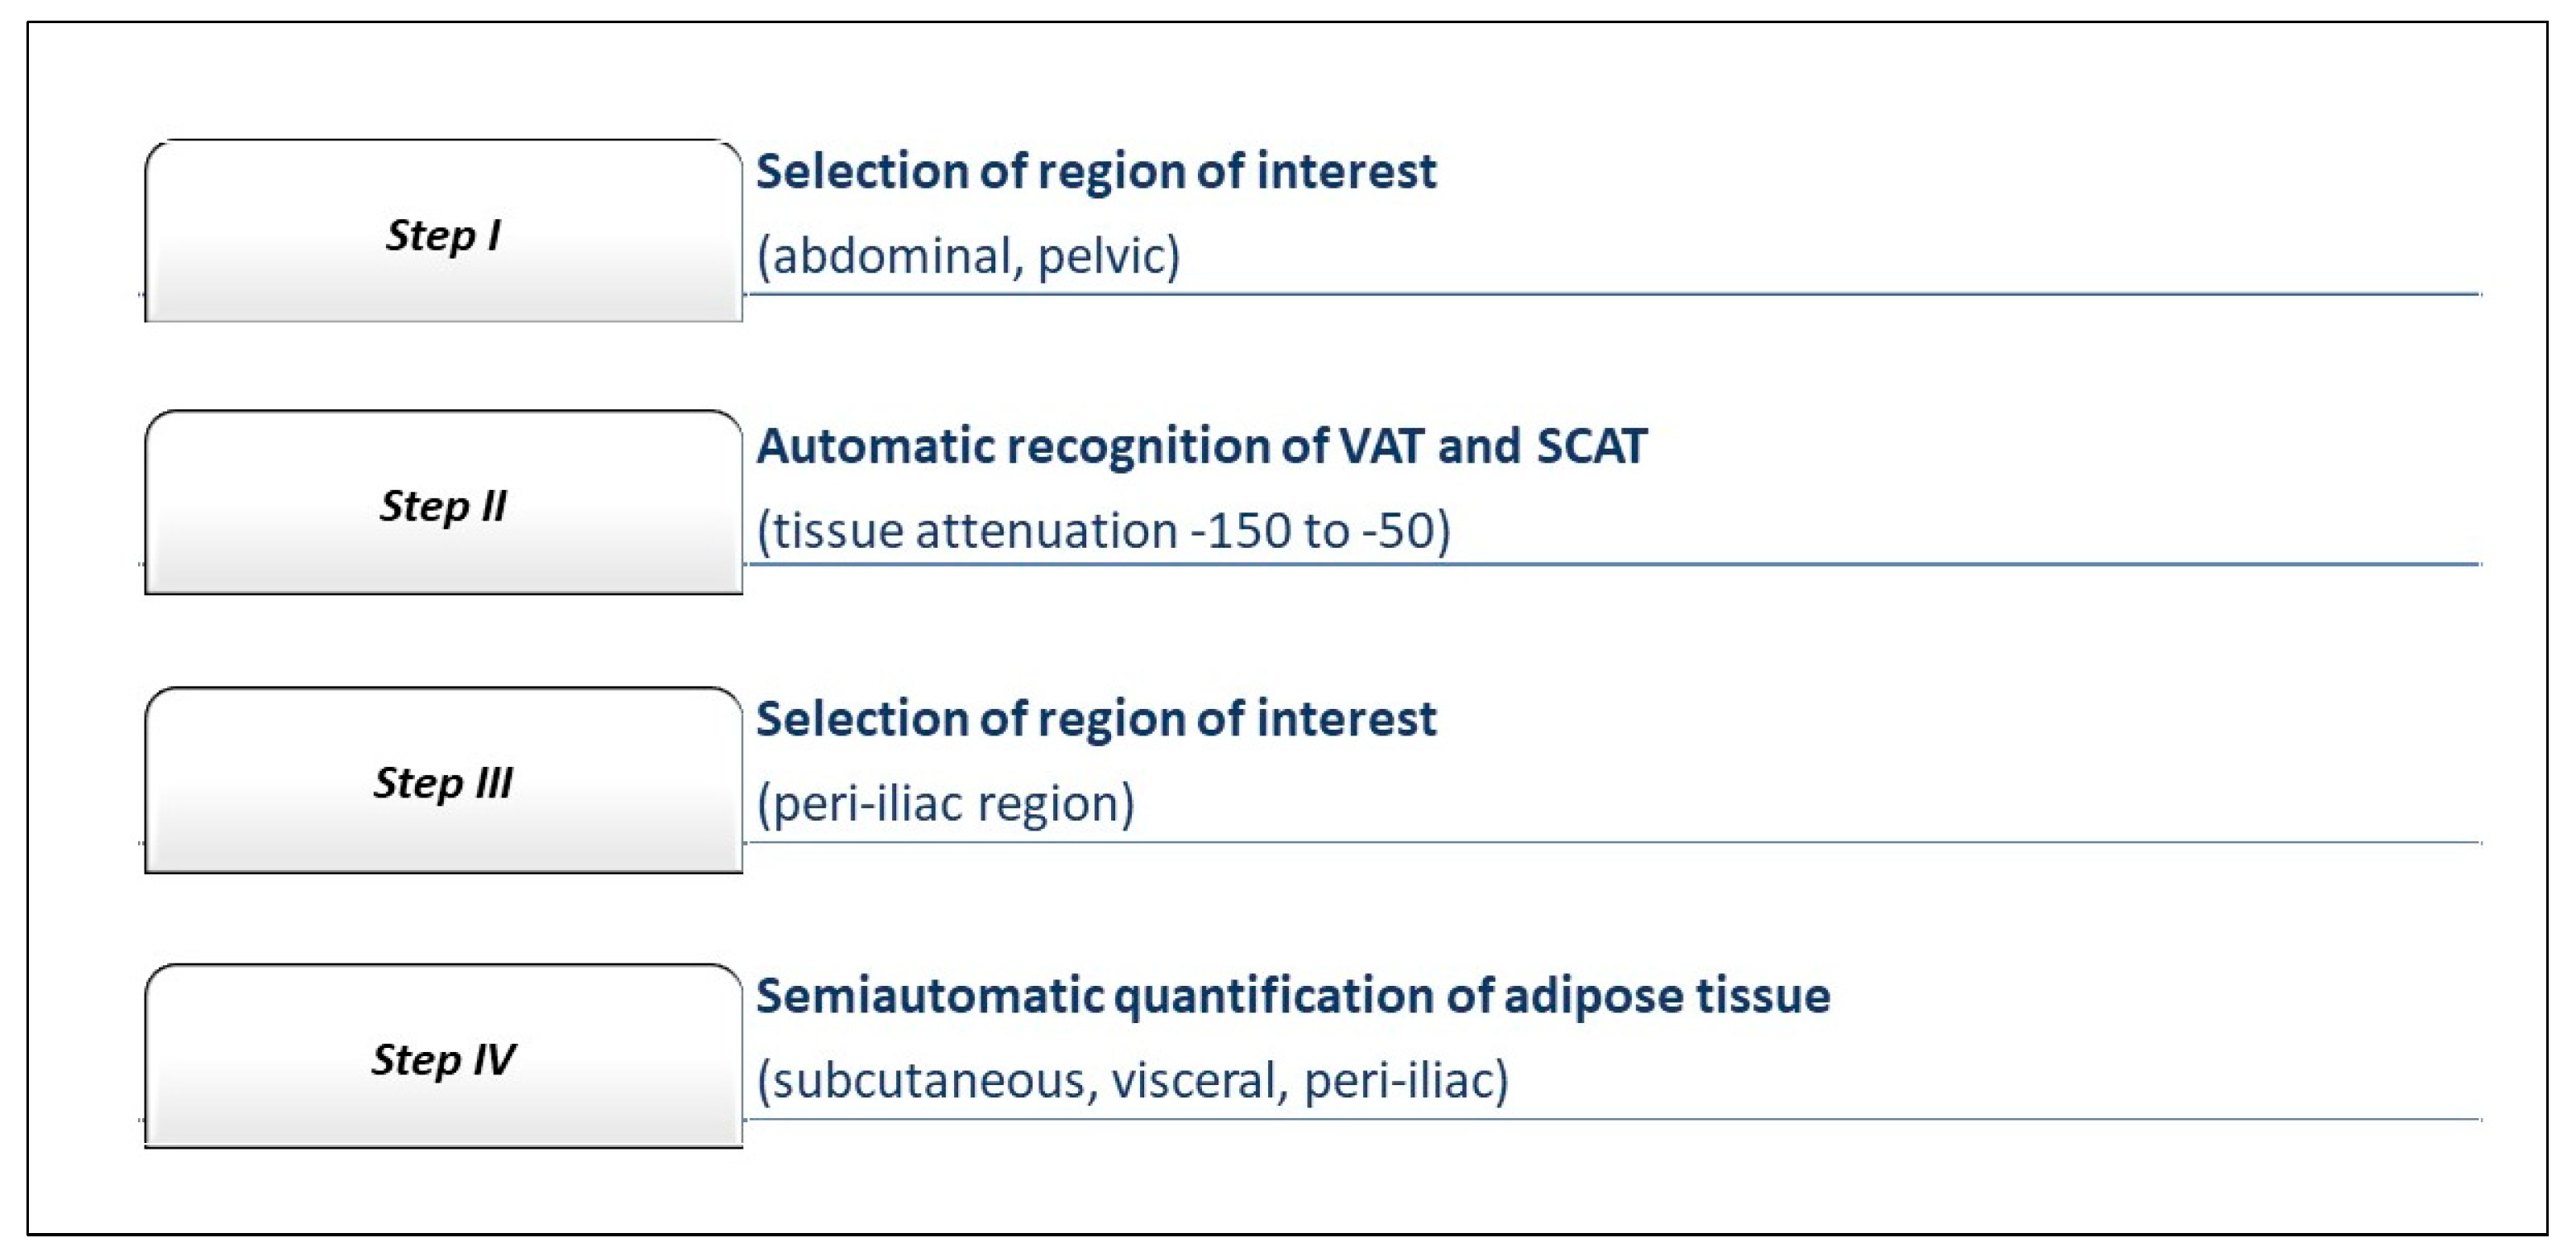

2.2. Computer-Aided CT Image Postprocessing

2.3. Assessment of the Periiliac Adipose Tissue

2.4. Assessment of The Subcutaneous and Visceral Adipose Tissue